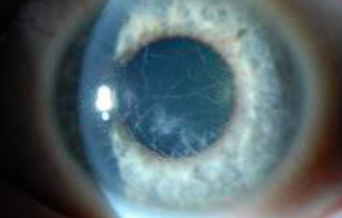

Lattice dystrophy